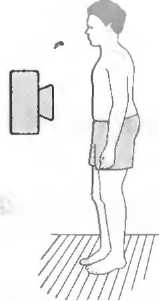

1. Подготовка

Пациент не должен пить и есть в течение 8 ч перед исследованием. Если жидкость необходима для предотвращения дегидратации, можно давать пациенту только воду. При острой симптоматике исследование можно проводить без подготовки. Детям, если позволяют клинические условия, пища и вода не даются в течение 3 ч до исследования.